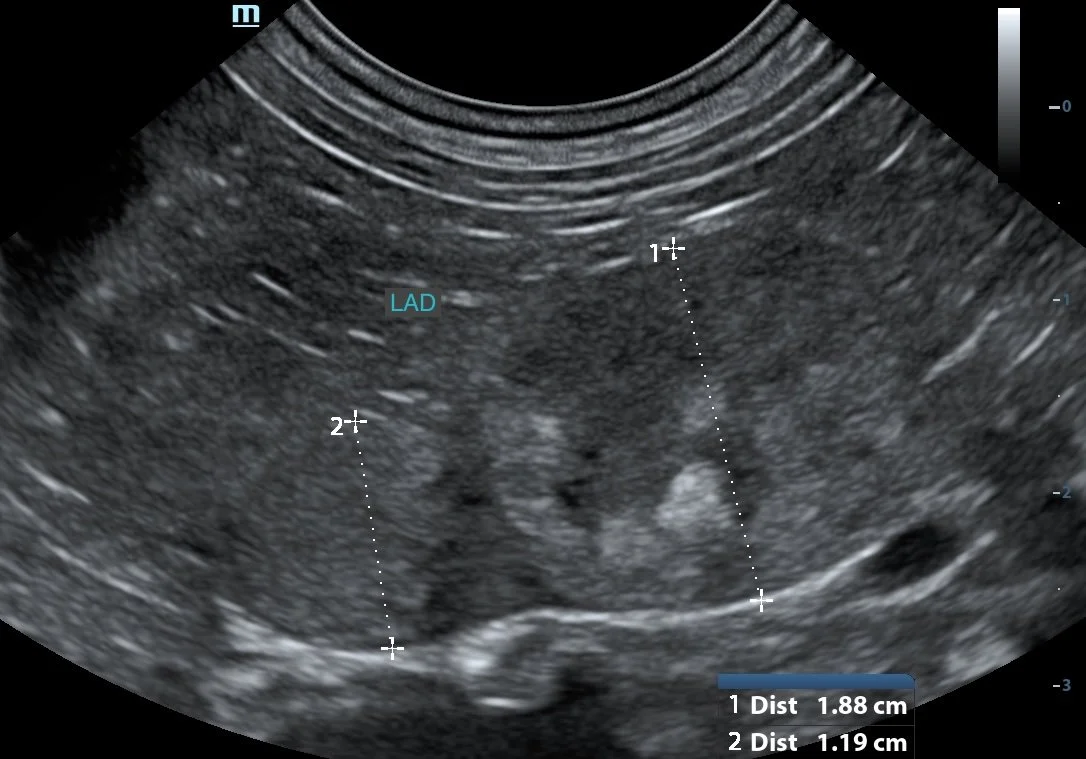

WATCH HOW IT ACTUALLY CAN LOOK IN PRACTICE

• reliably locate adrenal glands using consistent anatomical landmarks

• recognise normal vs abnormal with more confidence